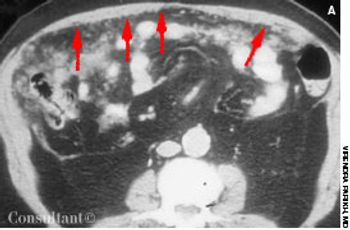

Vague abdominal pain, malaise, anorexia, and the loss of 10 lb in 2 months prompted a 65-year-old man to seek medical evaluation. A year earlier he had undergone surgery for stage III carcinoma of the sigmoid colon. Because metastases to the lymph nodes were found in the resected colon, the patient was given postoperative chemotherapy. Histologic examination revealed poorly differentiated adenocarcinoma.